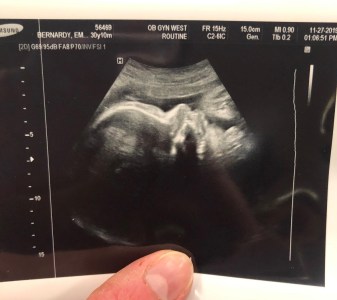

On Wednesday of this week we had our 36-week doctor appointment – the first of the final weekly appointments leading up to the birth of our child. At this appointment, we had an ultrasound, as I have had a sneaky suspicion that our little one is breech. Well, the ultrasound indeed confirmed this. We then had an in-depth conversation with my doctor about our options: either we schedule a C-Section, or we attempt what is called an External Cephalic Version (ECV) to flip the baby into a head down position. My goal is and has always been to have a vaginal delivery, if it is medically safe, so we decided we would like to attempt the ECV. The procedure is scheduled for this coming Monday. I will check in to the Labor and Delivery unit at our hospital at 7:30am, have an IV started, and receive a dose of a medication to relax my uterus (I wish it could relax my nerves, too!!). Then, with ultrasound guidance and fetal monitoring, our doctor will attempt to maneuver the baby into the birthing position. When I asked what to expect, my doctor was very transparent and stated it would be quite painful/uncomfortable, but we will take as many breaks as I need. I can’t help but feel anxious! There is about a 50% chance of it being successful, and if it is not, we will go ahead and schedule a C-Section. I have to remind myself that no matter the outcome on Monday, our ultimate goal is simply to deliver a healthy baby. Prayers, however, would be greatly appreciated! 😊